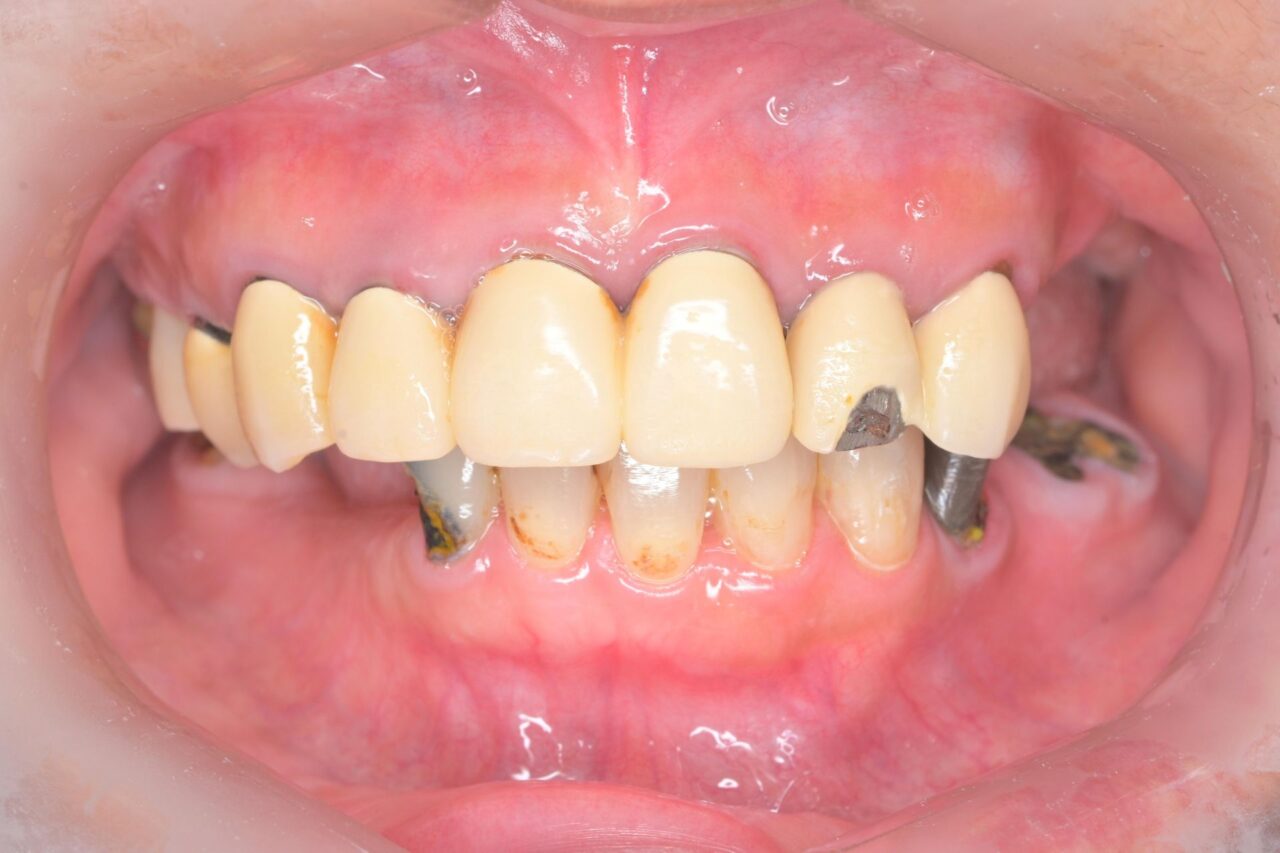

治療前

正面

上の前歯が完全欠けてしまっています。欠けている所だけを補修することもできるのですが、色が違ったり、すぐに取れてしまったりしておススメではありません。ってことで、毎度お馴染みの全部やり替えです。